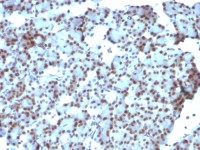

FACS analysis of mouse peripheral blood platelets using GTX43614 CD36 antibody [MF3] (FITC).